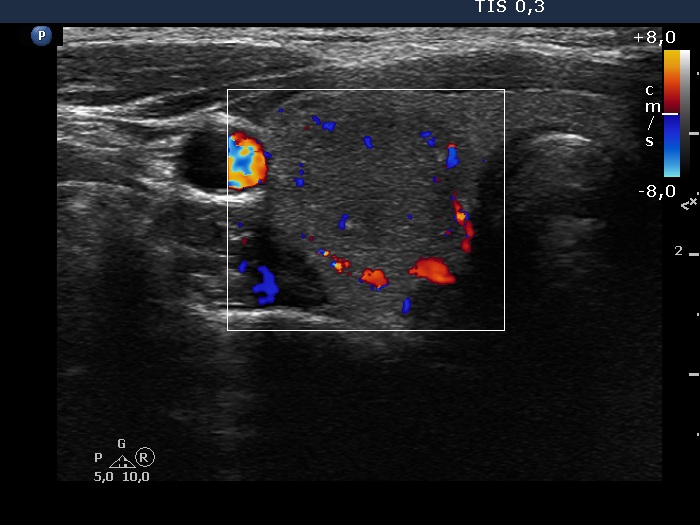

Ultrasonography. The thyroid was echonormal. There were two moderately hypoechoic nodules in the right lobe. They presented microcalcifications, the larger one ha irregular, lobulated margins. The nodule has grown significantly since the previous visit, from 8x8x15 mm to 14x12x20 mm, width, depth and length, respectively.